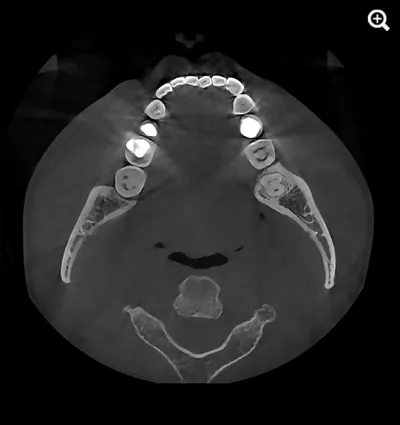

When capturing a CBCT scan, the presence of metal in the oral cavity can introduce artifacts, shadows, and bright streaks that significantly compromise image quality. These distortions may obscure critical anatomical structures, making it more difficult to evaluate bone integrity and surrounding areas—adding complexity to diagnosis and increasing clinical stress.

HDX WILL’s cutting-edge technology now offers a powerful solution through PrecisionMAR™, a metal artifact reduction feature that enhances clarity and ensures more precise imaging—even around metal. This is especially valuable for both dental professionals and ENT specialists focused on comprehensive treatment planning, including airway-focused care.

Minimizes scatter for cleaner imaging

Reduces shading and streak-related artifacts

Clearly defines bone and dental structures adjacent to metal

With improved image fidelity, practitioners can more confidently diagnose conditions, plan treatments, and support airway health initiatives critical to both dental and ENT fields.